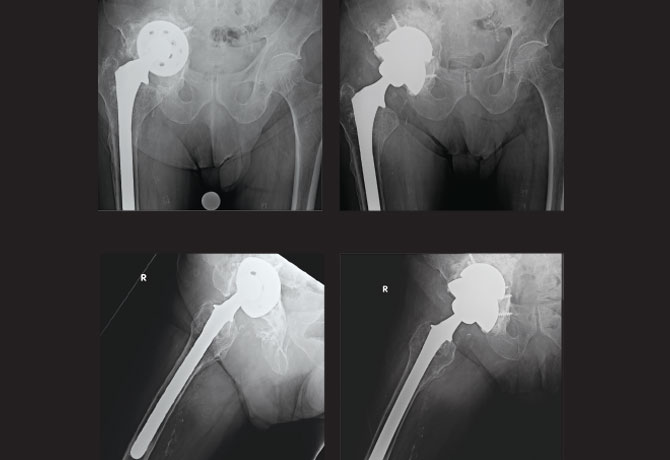

The patient is an 84-year-old male with a previous medical history of advanced cardiac disease (ejection fraction 15 percent), stage 4 chronic kidney disease, and a history of multiple myeloma and thyroid cancer, both now in remission. He fell off his bicycle in 1976 and underwent open reduction/internal fixation of right hip fracture. Ten years later, he underwent a total hip replacement followed by revision surgery in 2006.

About two years prior to his referral to Calin S. Moucha, MD, Chief of Adult Reconstruction and Joint Replacement Surgery, The Mount Sinai Hospital, and Associate Professor of Orthopaedics, Icahn School of Medicine at Mount Sinai, the patient began having progressively worsening right groin pain that reached 9/10 in intensity, difficulty ambulating without a walker, as well as significant pain putting on his shoes.

His physical exam was significant for an antalgic gait, limited motion throughout the right hip, and a flexion/external rotation contracture. Stinchfield test and Trendelenburg sign were both positive. Shortening of the affected limb was noted. Pulses were palpable and neurological function was fully intact.

Radiographs showed a well-fixed cementless revision femoral component. Loose revision acetabular component was visualized with complete destruction of the teardrop, violation of Kohler line, and migration > 3 cm superior to the obturator line. Superior-medial migration of the acetabular component was visualized on radiographs defining a Paprosky Type IIIB defect. CT scan confirmed no lytic lesions or periosteal formation suggestive of multiple myeloma or metastatic thyroid disease. Infection workup was negative.

The complexity of the case from an orthopedic and medical standpoint was explained in detail to the patient and his family. The patient was taken to the operating room for revision surgery under general anesthesia and an epidural.

The femoral stem was well-fixed and well-positioned. The acetabular bone stock, as predicted, was creating pelvic discontinuity. Dr. Moucha reconstructed the pelvis using a 62mm revision trabecular metal shell press fit into the superior defect, bone grafting using cancellous bone, followed by an 80mm revision trabecular metal shell placed inferiorly in distraction. Multiple screws were placed including into the ischial spine as well as in remaining areas of bone. The shells were unitized using antibiotic loaded cement. The liner was cemented into appropriate anteversion (a few degrees more than the shell), and a 40mm head was used to optimize stability.

His postoperative course was uneventful. The patient was allowed to bear weight as tolerated with a walker for eight weeks, followed by unassisted weight bearing as tolerated thereafter. At the latest 19-month follow-up, the patient’s radiographs showed a stable construct. He was ambulating pain-free without any assistive devices and enjoyed getting back to gardening.